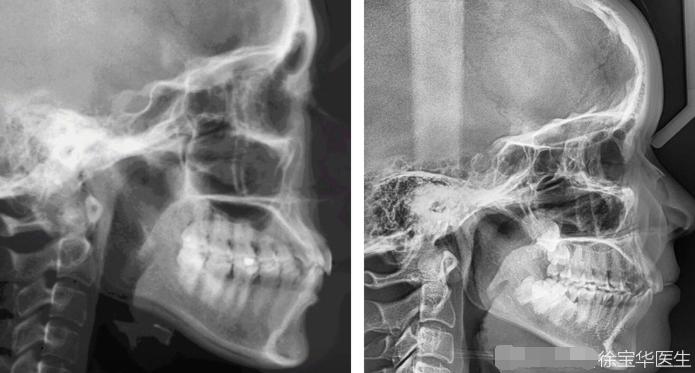

我们必须搞清楚嘴凸是是骨性的还是牙性的,同时要计算骨性畸形的程度,只有严重骨性牙颌畸形才会选择正颌手术治疗,在临床病例里,分辨骨性和牙性有个专有名词叫ANB角,这个角是通过X线投影测量技术计算得出的,一般这个角大于5°就应该是骨性畸形,当ANB角达到8°以上就属于严重骨性畸形。

骨性嘴凸相当于上下骨头基座出了问题,头影测量ANB角大。有些目测外貌较明显的嘴凸特别容易混淆概念,误以为是骨性的嘴凸,此处有些认识的盲区,不但患者会认为自己是骨性嘴凸,甚至很多医生也会把牙根凸误认为是骨性嘴凸。如果上颌骨不凸、鼻基底不凸,就不是纯骨性的。所以面诊外貌时会看鼻基底、摸牙槽骨处牙根的位置,分清楚牙槽骨处是牙根凸还是真正的骨性的嘴凸,事实上牙根的位置的凸起并不是真正的骨性嘴凸。也就是说,通过专业的正畸方案,大部分都可以获得比较好的矫正效果,免去了正颌的痛苦。